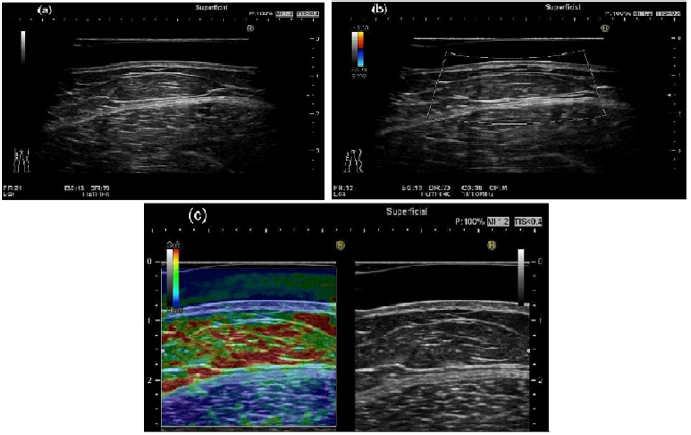

Figure 2: Panniculitis comprehensively diagnosed in the lower extremity location in a 62-year-old woman. Figure 2 demonstrated US features using equipped with acoustic coupler (SF-001).

(a) The septal, showing thickening of the hypodermis with fatty lobules and thick hypoechoic septa in between the fatty tissues were shown on gray-scale US.

(b) There are a few blood flows signals on color Doppler US.

(c) The blood flow signals on Fine Flow were also shown.